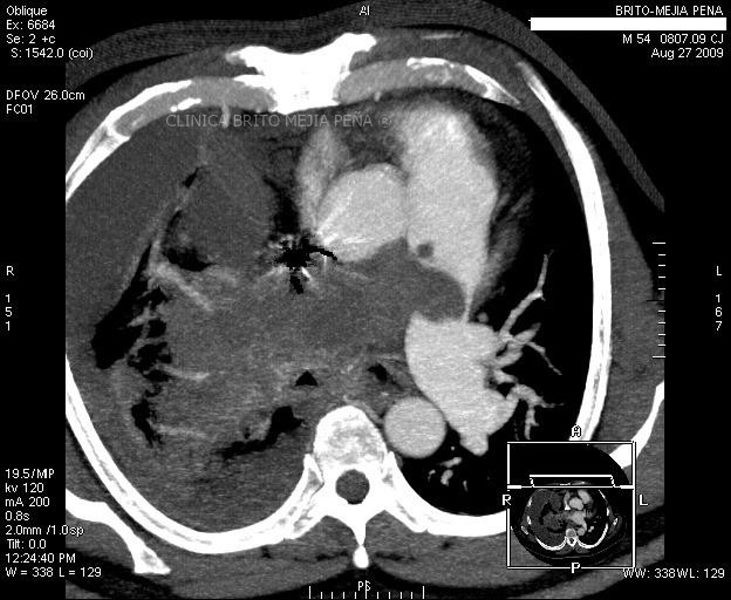

Tumor de esófago oblicua